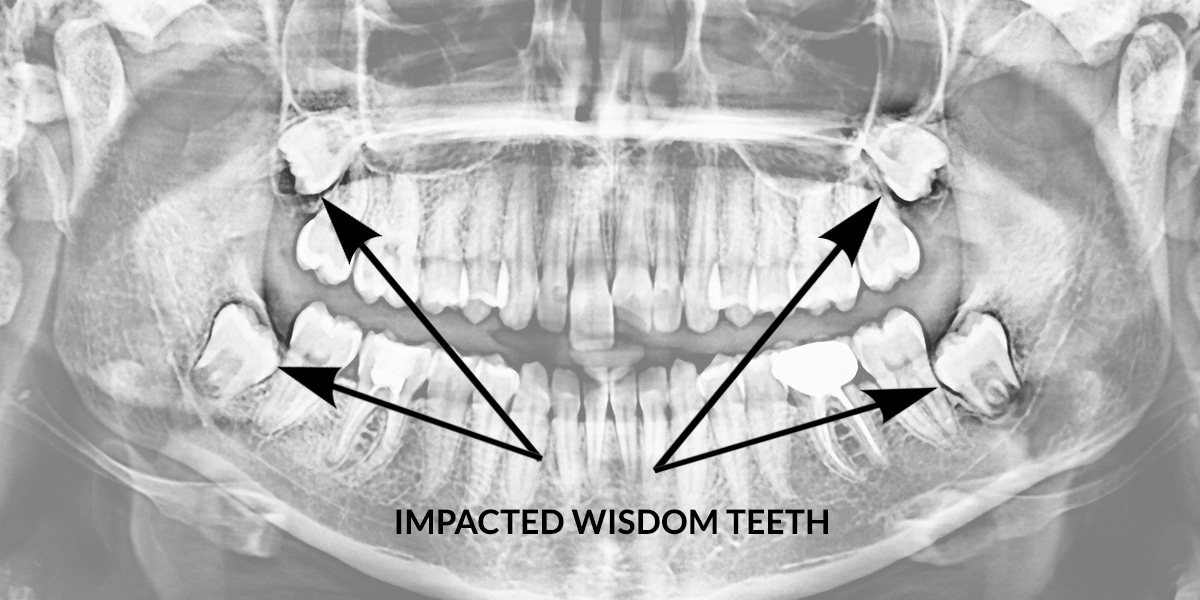

Why Wisdom Tooth Removal May Be Necessary